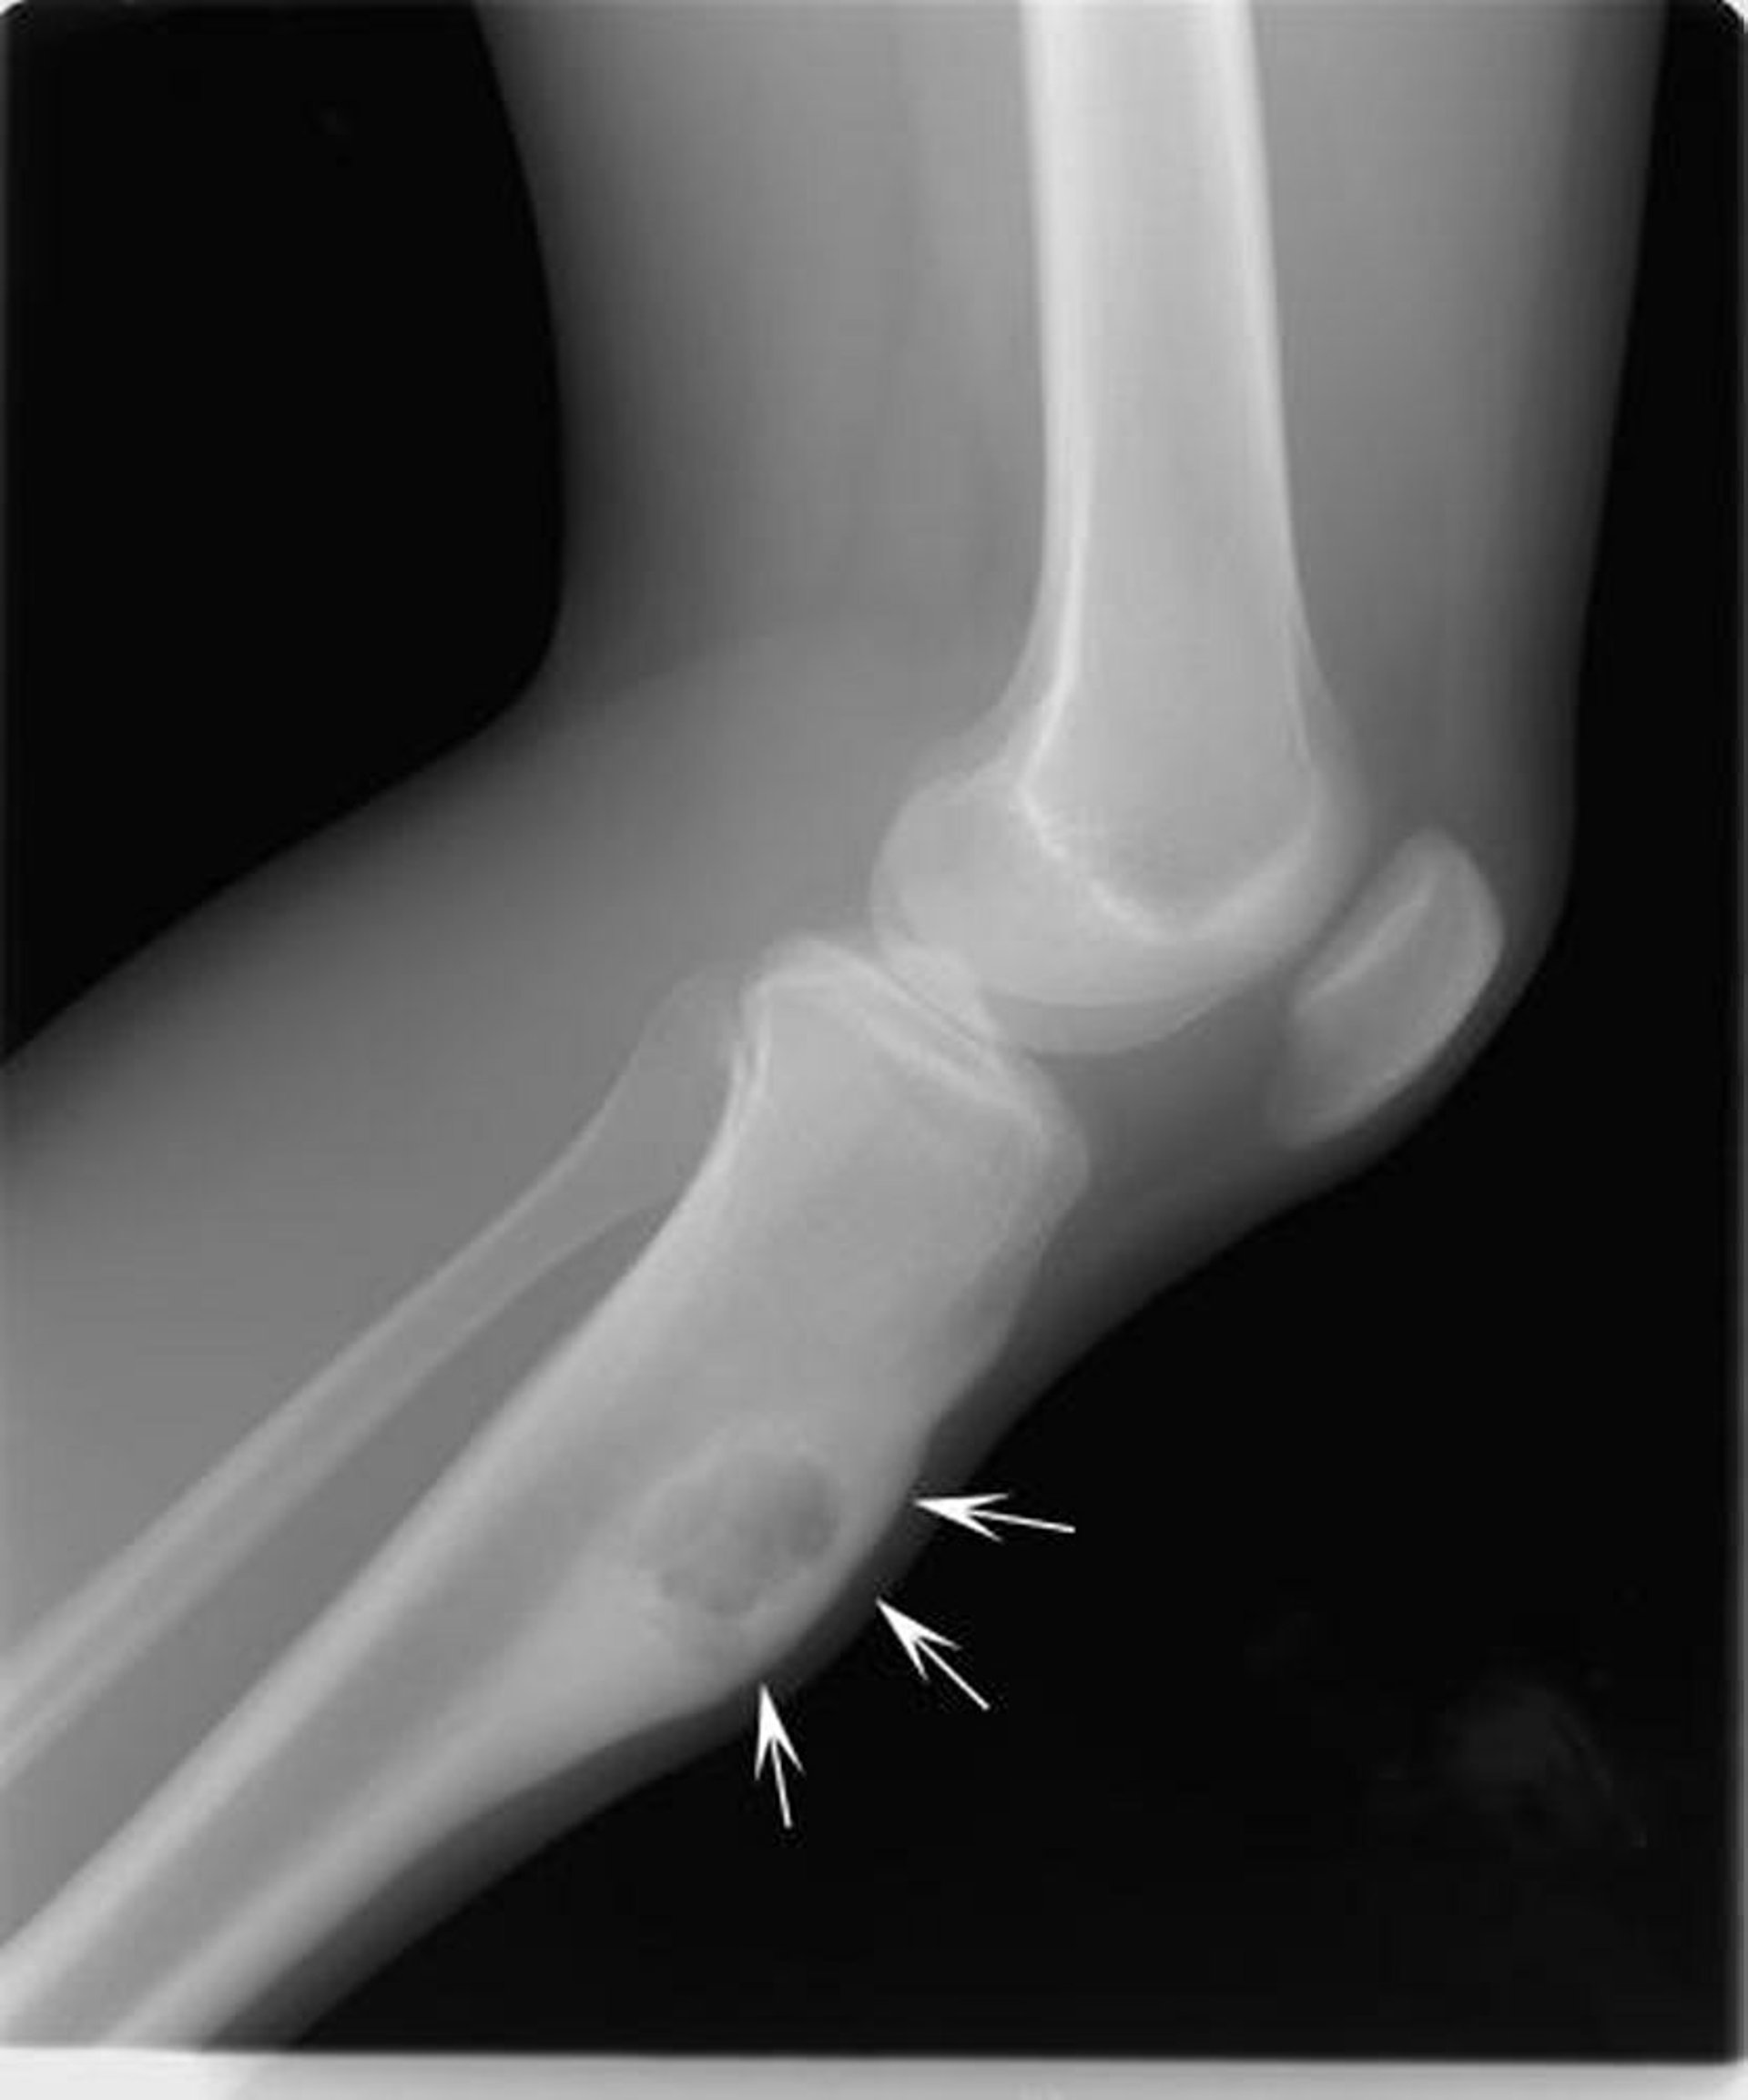

Dieses Röntgenbild des Knies zeigt ein chondromyxoides Fibrom in der Tibia unterhalb des Knies (Pfeile), das den Knochen in der Front ausdehnt.

Image courtesy of Michael J. Joyce, MD, and Hakan Ilaslan, MD.